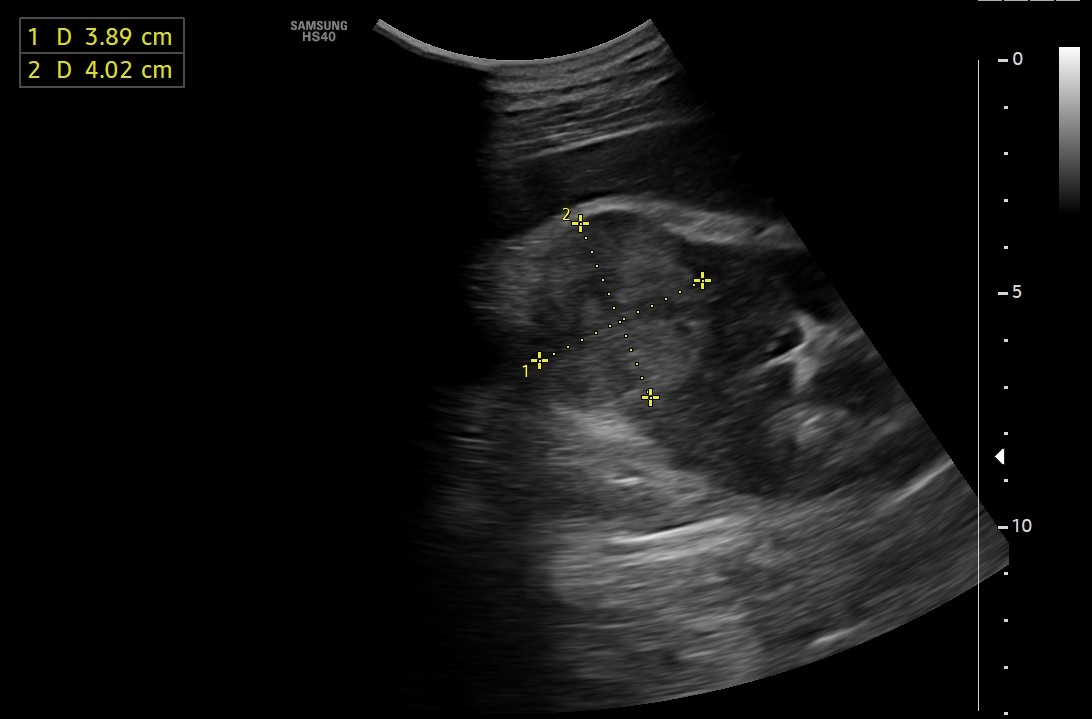

Se realiza ecografía para valorar tamaño prostático.

Hallazgos ecográficos

Hallazgos ecográficos: lesión sólida exofítica de márgenes bien definidos en la región interpolar posterior del riñón derecho, hiperecogénica respecto a la cortical renal, con vascularización interna en el estudio Doppler y unas medidas aproximadas de 45 x 40 mm.

Próstata aumentada de tamaño, con unas dimensiones de 55x65x56 mm que se corresponden con un volumen de 106 cc (hipertrofia prostática grado IV).